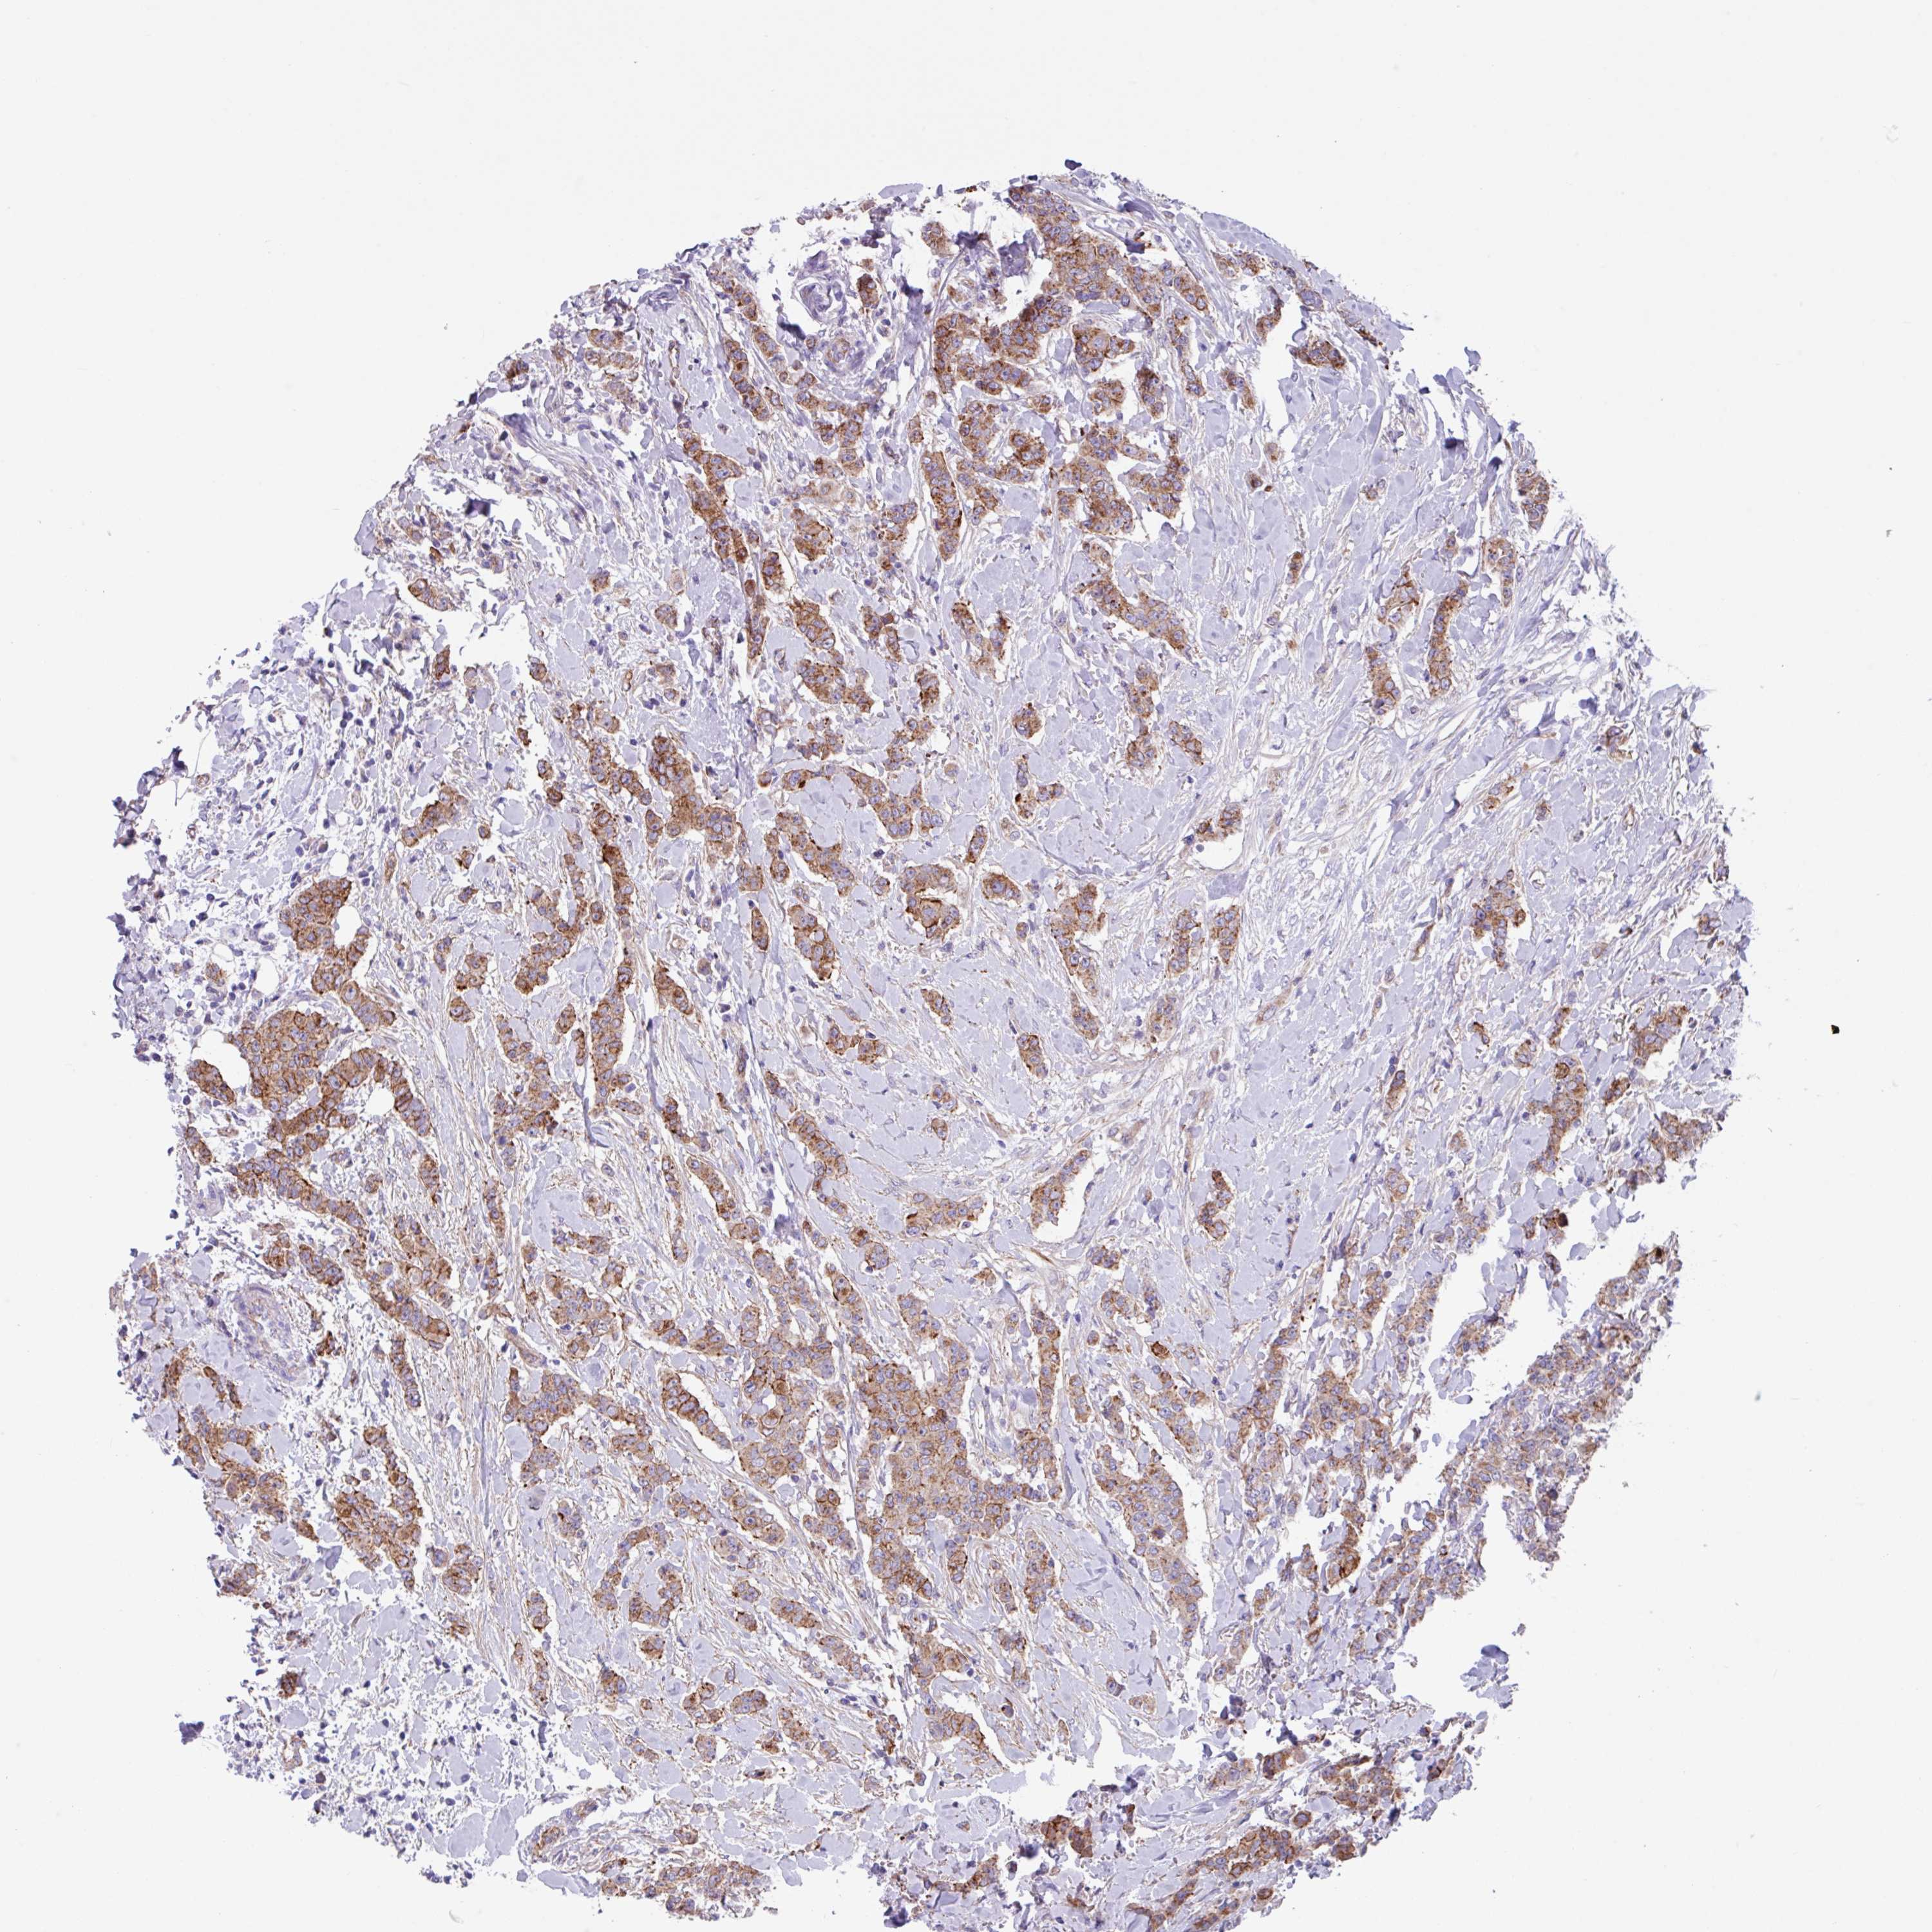

CANCER BREAST CANCER Show tissue menu

BRCA TCGA BRCA VALIDATION PROTEIN EXPRESSION

Breast cancer

Human cancer